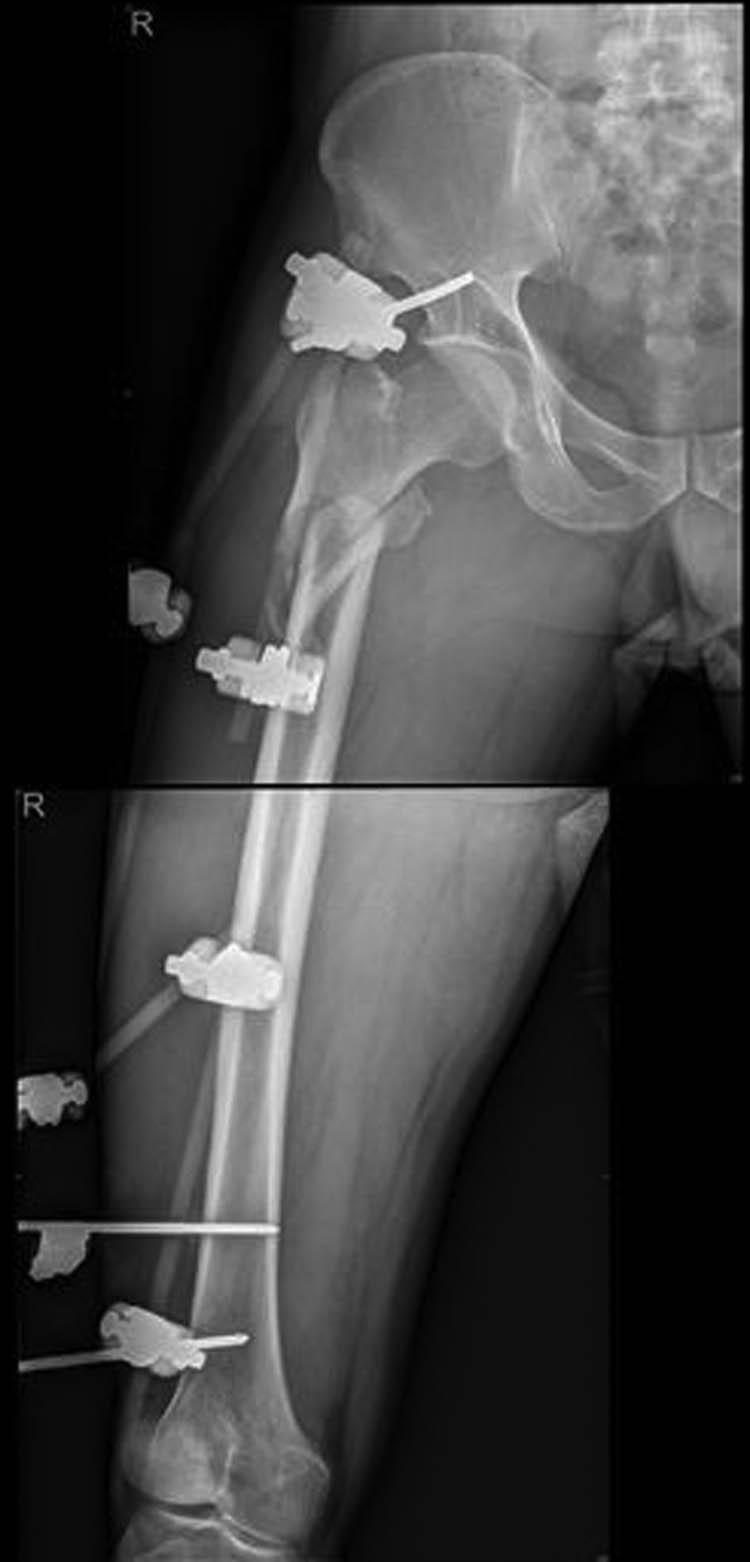

External fixation via the AIIS and distal femur was performed by a single surgeon under general anesthesia without regional nerve blockade during emergency surgery. External fixators derived from AO (Synthes, Ltd., Paoli, PA), Trauson (Trauson, Ltd., Changzhou), and Carefix (Carefix, Ltd., Shanghai) were used. Patients were placed in a supine position on the operating table. A C-arm was used to locate the points of the AIIS, and a minimal incision of 1–2 cm in length was made. The deep fascia of the pelvis and femur were incised. Proximally, the lateral femoral cutaneous nerve was protected by a surgical hook. One pin (diameter 6.0 mm, length 180 mm, thread length 60 mm) was placed at the AIIS on the same side as the PFF. Distally, two crossing pins (diameter 6.0 mm, length 180 mm, thread length 60 mm) were placed at the distal femur through two minimal incisions. High-strength and fully transparent carbon fiber rods (diameter 8 mm, length 400 mm) were fixed, manipulative reduction was performed along the strength line under the C-arm, and the clamps were tightened. The incisions were then sutured. A typical case is presented in Figures 2–5.

Postoperative X-ray showing good alignment following external fixation.